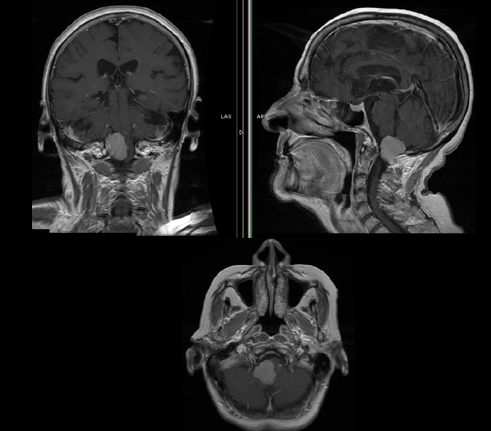

图1:

术前对比增强磁共振成像(MRI)图像显示明确定义的双侧增强病变。神经被夹在病变之间并被严重压迫(a)轴性:双孔增强的双侧大块病变,(b)矢状位MRI,(c)冠状位MRI,(d)计算机断层血管造影显示病变与椎骨的关系动脉。